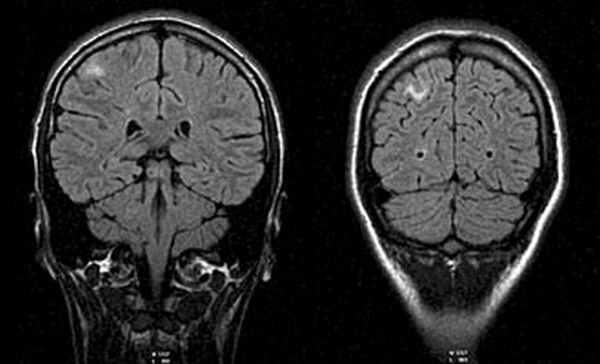

МРТ головного мозга (11.03.08): в белом веществе головного мозга субкортикально в лобно-теменной области справа определяются округлые и линейные очаги с перифокальным отеком размерами от 3 до 10 мм.